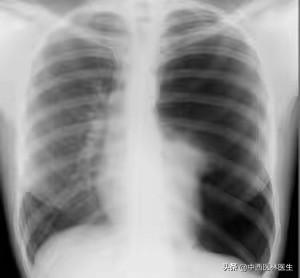

Par exemple, si vous souffrez de la toux sèche la plus courante, la première chose à envisager est qu'elle soit causée par une maladie respiratoire.figure ci-dessous), il s'agit souvent d'un moment où les symptômes de la toux ne sont pas les seuls à se manifester, souvent accompagnés d'autres symptômes avant ou pendant le processus.

- Infections des voies respiratoires supérieures.Le virus pénètre dans l'organisme par le nez et la gorge et provoque une inflammation des muqueuses des voies respiratoires supérieures ;

- Bronchite.Il s'agit souvent d'une infection de longue durée des voies respiratoires supérieures qui n'est pas guérie, ou de la propagation de la toux, le début d'une toux sèche, suivie d'un reflux des sécrétions, peut entraîner une toux de mucosités et d'autres désagréments, et dans les cas graves, vous pouvez également ressentir de la dyspnée ;

- inflammation des poumonsLa toux sèche est également présente, mais cette fois-ci, elle a tendance à être plus longue, accompagnée d'un essoufflement, etc.figure ci-dessous(ibid.).

En temps normal, la toux est l'un des symptômes les plus courants du système respiratoire. Le rhume, la bronchite, l'asthme, la pneumonie, la tuberculose, la dilatation des bronches, le pneumothorax, l'emphysème et le cancer du poumon peuvent être à l'origine de la toux, de la toux sèche. Dans le traitement de la toux sèche, nous devons d'abord identifier la cause de la maladie, puis les symptômes et la cause profonde de la maladie, afin de guérir rapidement, efficacement et complètement la maladie.